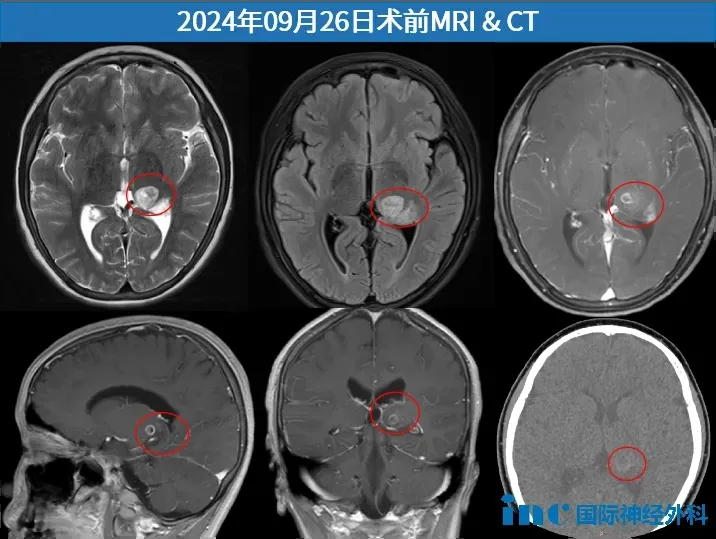

小杰的病灶恰好位于基底节区中央,与运动神经纤维相连,非常隐蔽的地方,而且很重要的区域,手术非常具有挑战性。因此,为了保护孩子的运动功能,巴教授建议术前进行DTI重建,图像会显示出运动纤维在肿瘤的哪个部位。这样主刀在手术时就能更加小心,避免误伤到它们。

术前,巴教授查看小杰的DTI重建